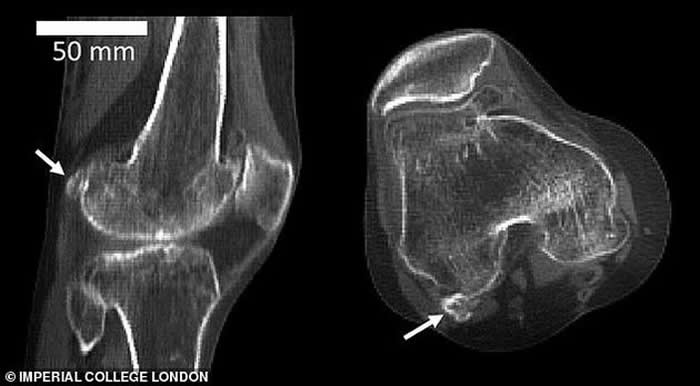

图中显示3个不同膝骨样本存在不同大小的豆骨。科学家发现1918年全球11.2%居民体内存在豆骨,但截至2018年,全球39%居民体内存在豆骨。

英国伦敦帝国理工学院的研究人员回顾了过去150多年进行的2.1万多项科学研究,其中包括研究人员扫描和解剖鉴定发现豆骨的存在。他们从中发现1918年全球11.2%居民体内存在豆骨,但依据发表在《解剖学杂志》的这篇评论报告,截至2018年,全球39%居民体内存在豆骨。

伯托姆博士称,当远古灵长目动物进化成大猿和人类,我们似乎已不再需要豆骨,现在它只会给我们带来麻烦,但有趣的是,近年来人体出现豆骨的概率骤增。这项最新研究发表在《解剖学杂志》上,作者详细研究了25个国家21676个膝盖数据,最早的数据可追溯至1875年。这些膝盖数据来自多种渠道,其中包括:X射线、核磁共振扫描和局部解剖。